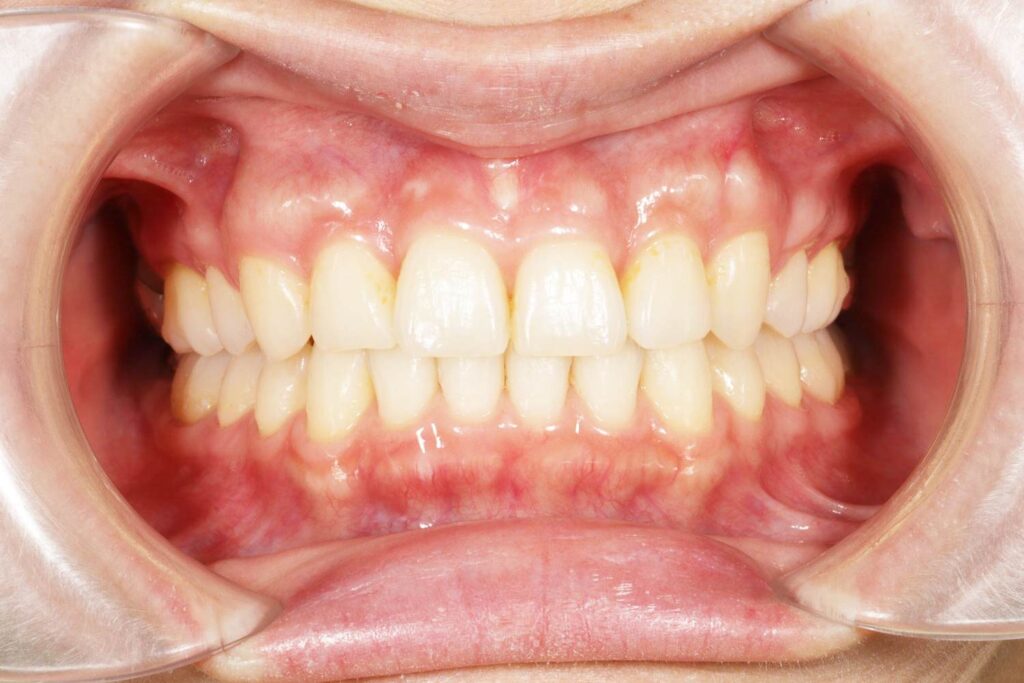

Before

After

年齢 10代

治療装置 上は裏側の矯正装置(フルリンガル)

治療内容 非抜歯

治療期間 2年8か月

リスク 歯の移動に伴う痛み、歯肉退縮、歯根吸収、歯肉炎、虫歯

主訴 ガタガタと隙間が気になる

症状 叢生と正中離開

治療回数 36回程度

総額費用 140万円程度